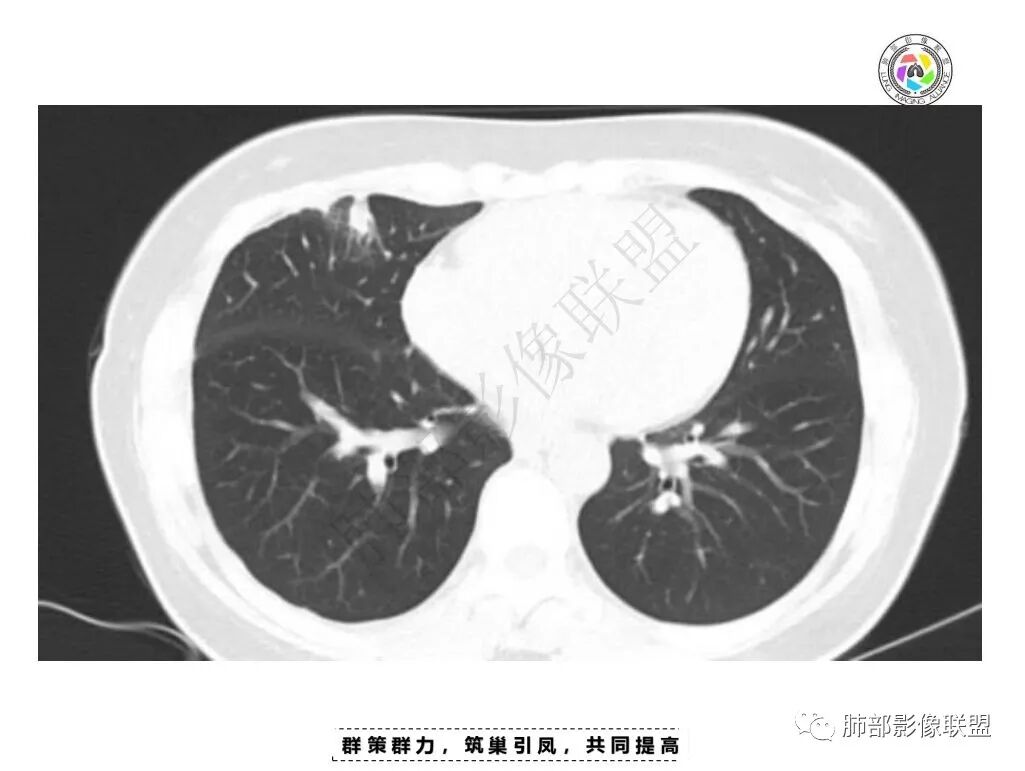

青年女性,胸痛1年,慢性病程

2.肺内多发斑片影,边缘光滑,支持炎性特点,不符合恶性侵犯的特点,一般恶性肿瘤侵犯肺内往往边界不清,复查附近病灶有收缩,更加支持炎性病变;

胸膜区病灶及肺内病灶符合炎性改变,支持一元论炎性。